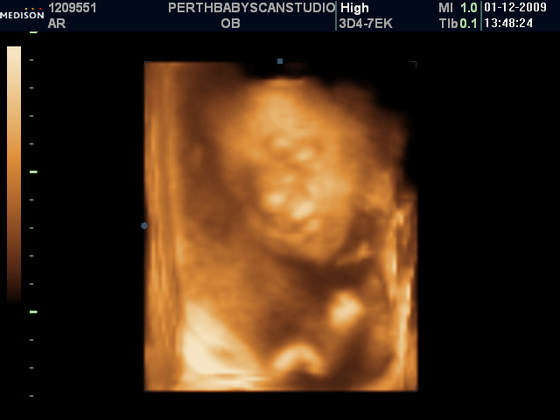

A mi gin w poniedzialek powiedzial, ze Mala wazy ponad 1000g!!! I, ze wg Niego, po wymiarach na usg i wygladu brzuszka, ciaza jest starsza o jakies 2 tyg.